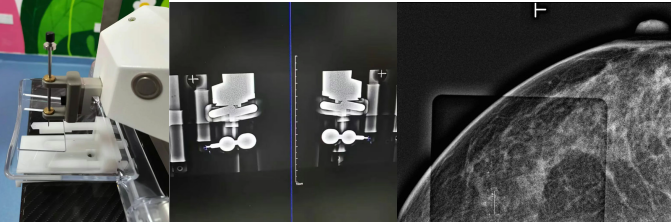

钙化灶在乳房中通常微小且无法直接触摸到。如何确保外科医生在手术中能精准找到这些“隐形目标”?这就是钼靶引导无可替代的作用:

精准定位: 在钼靶机实时透视下,将一根纤细的定位导丝准确穿刺植入到钙化灶的中心或紧邻区域。

路径规划: 医生会根据钙化位置和导丝入路,设计最合适、创伤相对小的手术切口。

标本验证: 手术切除包含导丝尖端(即目标钙化区域)的组织块后,需立即进行标本钼靶摄片。这是关键质量控制步骤